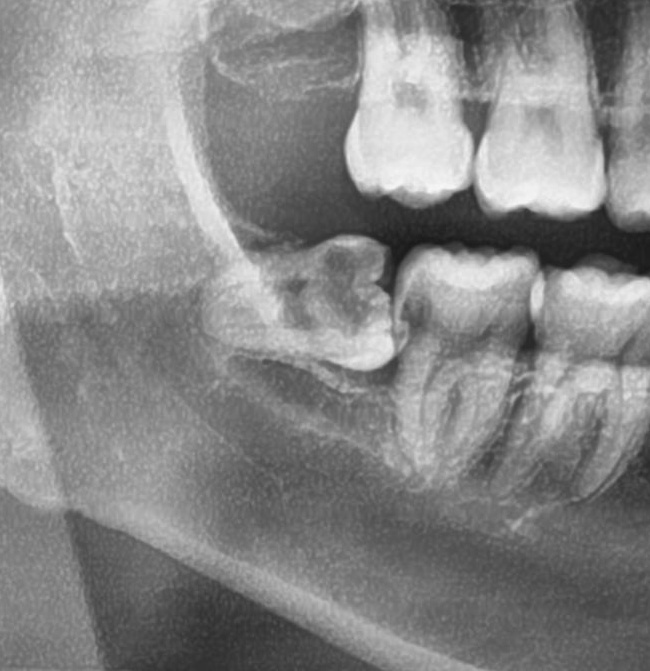

次に3番目の患者様。

左下の親知らずに入れていた詰め物が外れたため、今回抜歯することになりました。

頭もしっかり出ている状態でまっすぐに生えていたので、あっという間に抜歯終了。